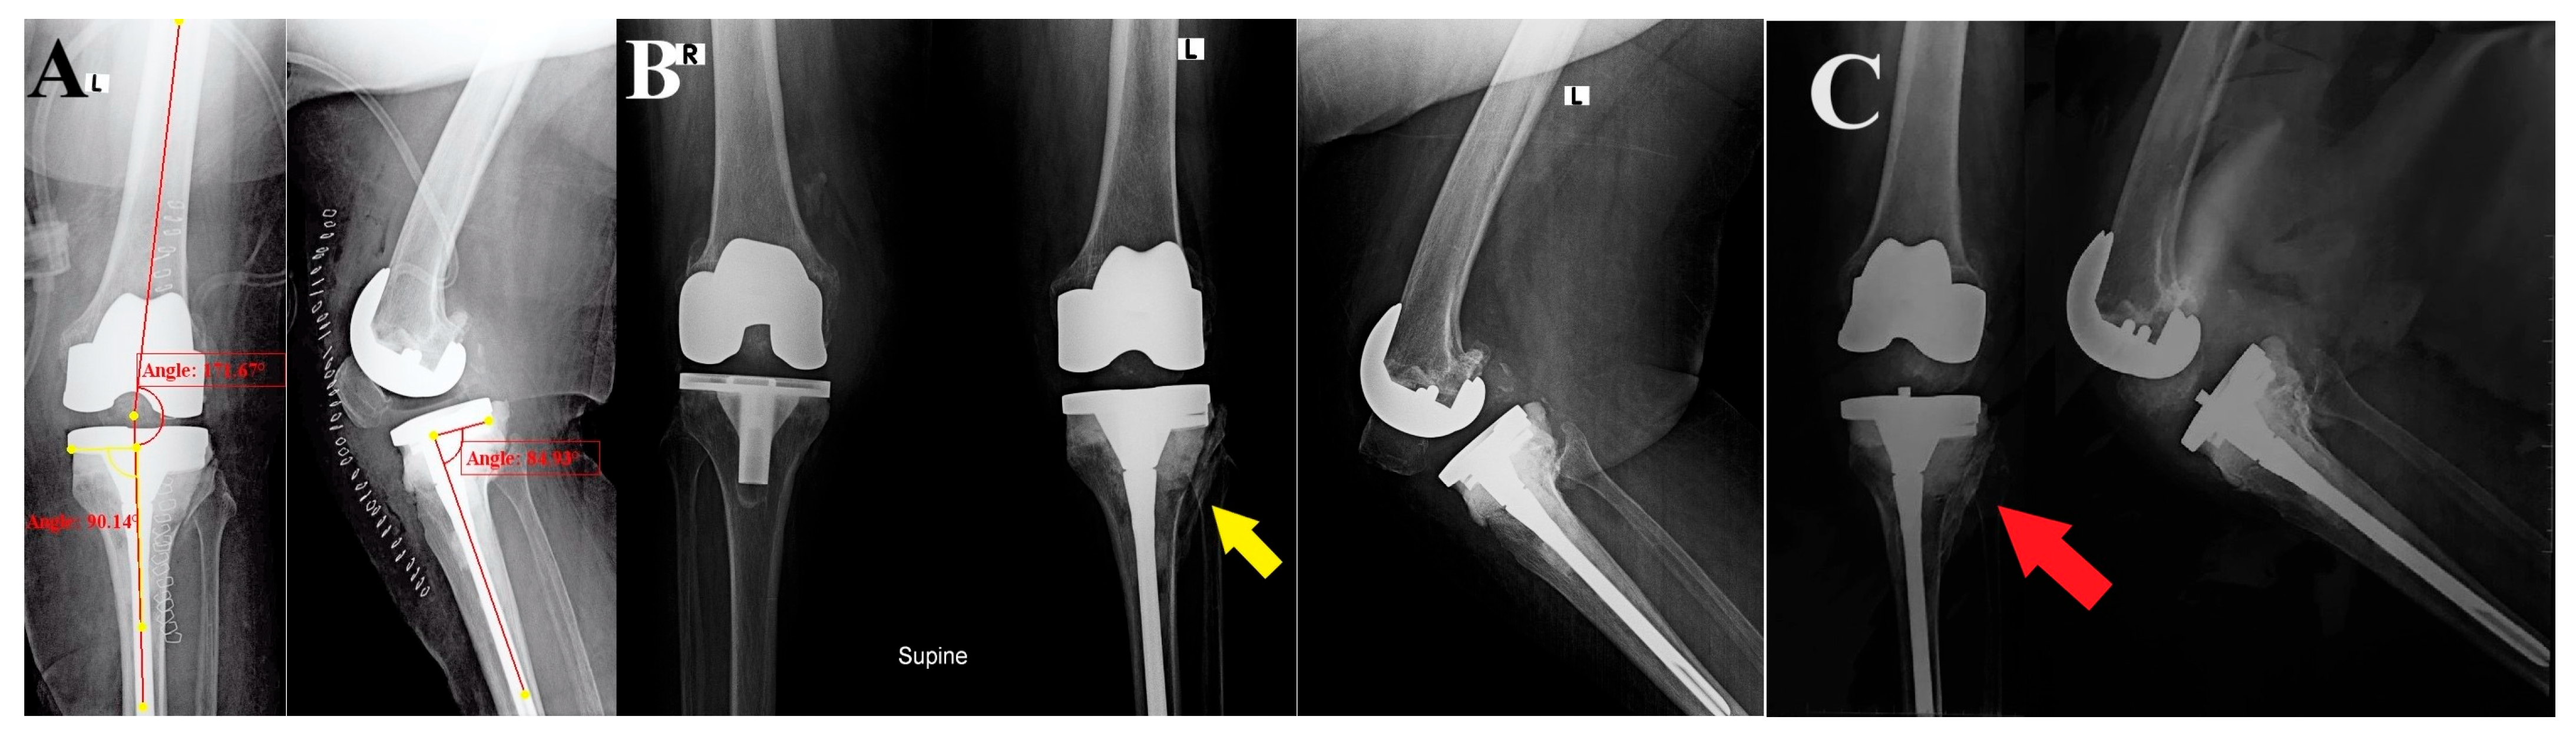

At two weeks, the staples were removed, and the surgical wound showed no signs of infection. After eight weeks of follow-up, the knee range of motion was from 0° to 100°, she reported satisfactory knee function according to Oxford Knee score (41 points), the radiographic assessment of the limb alignment and implant positioning was acceptable (aFTA: valgus 8°, posterior TS: 5°, and MPTA: 90°), and the lateral tibial plateau cortex fracture showed signs of healing and callus formation. The patient was unable to present at the clinic for further follow-up; upon contacting her (the last follow-up was at six months postoperative), she reported no advert incidents. The PROM outcomes in the form of Knee Injury and Osteoarthritis Outcome Score (KOOS) were assessed and a score of 72.6 was achieved, and she sent her last follow-up radiograph (Figure 3).

Figure 3. Postoperative and follow-up radiographs: (A) Immediate AP and lateral views of the revised TKA show the reconstruction of the lateral tibial defect, the restoration of the lower limb alignment, and proper implant positioning. (B) At eight weeks of follow-up, the limb and implant alignment was maintained, and the lateral tibial plateau cortex fracture showed signs of healing and callus formation (yellow arrow). (C) At six months of follow-up, the fracture showed healing (red arrow) and stable implants.